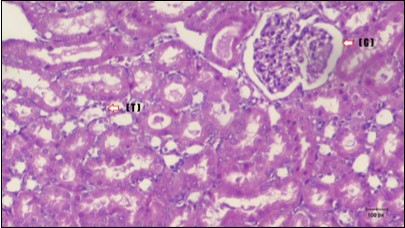

Kidney sections of diabetic rats showed an increase in mesangial cell and matrix of glomeruli with increase in glycogen deposition and hyalinization of arterioles with thickened basement membranes of proximal and distal convoluted tubules. These changes will lead to progressive reduction in the filtration surface of the glomeruli 35. Histological examination of the kidney of the control rats showed normal structure of renal glomerular. The proximal and distal tubules were lined with normal epithelium (Figure 13). The diabetic rats showed tubular casts, inflammatory cellular infiltration and glomerular atrophy (Figure 14). Kidney of rats in groups (3 and 4) showed some glomeruli return to be normal (G). Focal tubules casts (T) in Fenugreek group and some normal tubules in the Glimepiride group with no inflammatory cellular infiltrate in both groups (Figure 15 and Figure 16). However, kidney of rats in group (5) showed normal glomerular (G), normal tubules (T) with no tubular casts (Figure 17).

Figure 17.Photomicrogragh of kidney section of treated rat with both Fenugreek and Glimepiride showing improved cortical tissue with most of both Bowman,s capsules (arrow) and proximal tubules (dash-arrow) with nearly normal structure .Note distal tubules still suffering (star). (H&E) (40X).

Photomicrogragh of kidney section of treated rat with both Fenugreek and Glimepiride showing improved cortical tissue with most of both Bowman,s capsules  (arrow) and proximal tubules (dash-arrow) with nearly normal structure .Note distal tubules still suffering (star). (H&E) (40X).